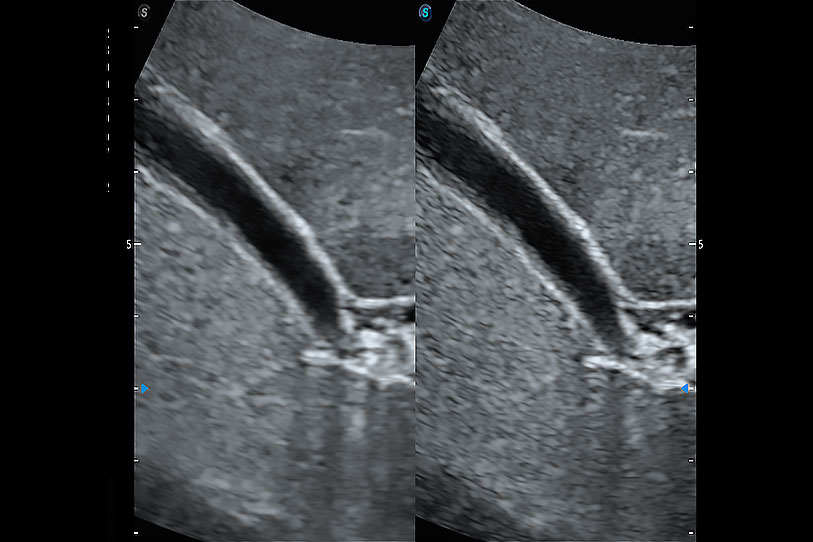

通过360度任意调节3条M型取样线,在同一心动周期上观察心脏不同位置的运动曲线,得到准确的心功能测量数据,有效评估心肌运动及左心室功能。